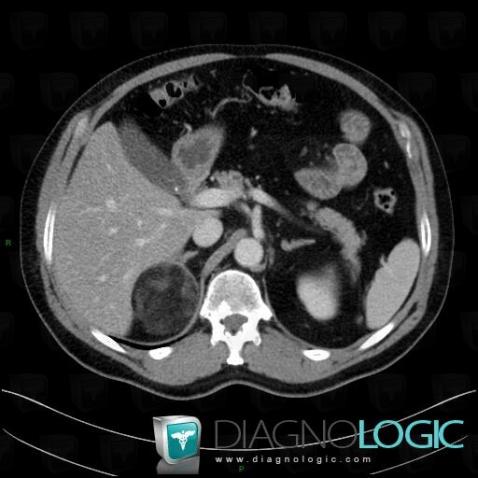

Myélolipome, Rétroperitoine, Scanner

Voici les informations spécifiques à l'image clé ci dessus:

- Diagnostic Myélolipome, Localisation(s) Rétroperitoine, comportant les gammes Lésion de l'espace péri rénal